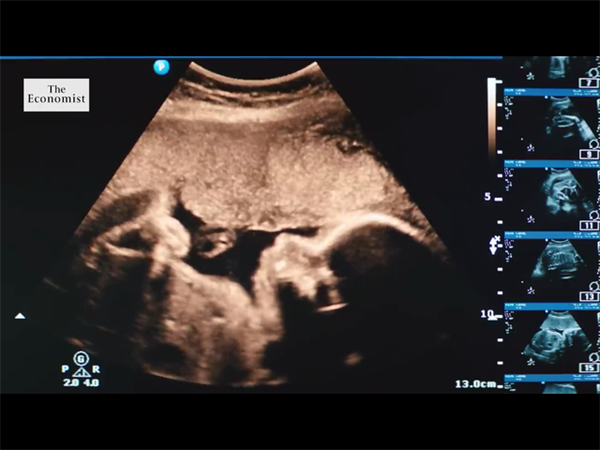

如今,隨著國家經濟的發展,出行也變得十分便捷,有不少不孕不育夫婦都會選擇到國外做試管嬰兒,其中,不少夫婦會選擇在格魯吉亞做試管,但相比于東南亞國家而言,大多數人對格魯吉亞相對陌生,那么格魯吉亞試管嬰兒有哪些優勢呢?下面來具體了解一下吧。

不少人之所以放棄在國內做試管,而選擇去格魯吉亞進行試管助孕,歸根結底還是看重了格魯吉亞試管嬰兒技術的優勢,不過很多不孕不育夫妻并不是特別了解,下面就為大家著重解釋一下格魯吉亞試管嬰兒6個絕對優勢完勝國內。

格魯吉亞試管專家介紹:國內醫院基本上是運用第一代和第二代試管,醫院人滿為患,排隊的周期還在不斷加長。所謂第三代試管嬰兒也稱胚胎植入前遺傳學篩查確診(PGS/PGD),指在胚胎移植前,取胚胎的遺傳物質進行剖析,確診是否有異常,篩選健康胚胎移植,防止遺傳病傳遞的辦法。

而據現在統計,全世界遺傳性疾病有4000余種,現在格魯吉亞的第三代試管嬰兒運用PGD技能最大程度篩查出125種遺傳性疾病,沒有任何的約束條件任何人都可以做,并且可以合法選擇生男生女。